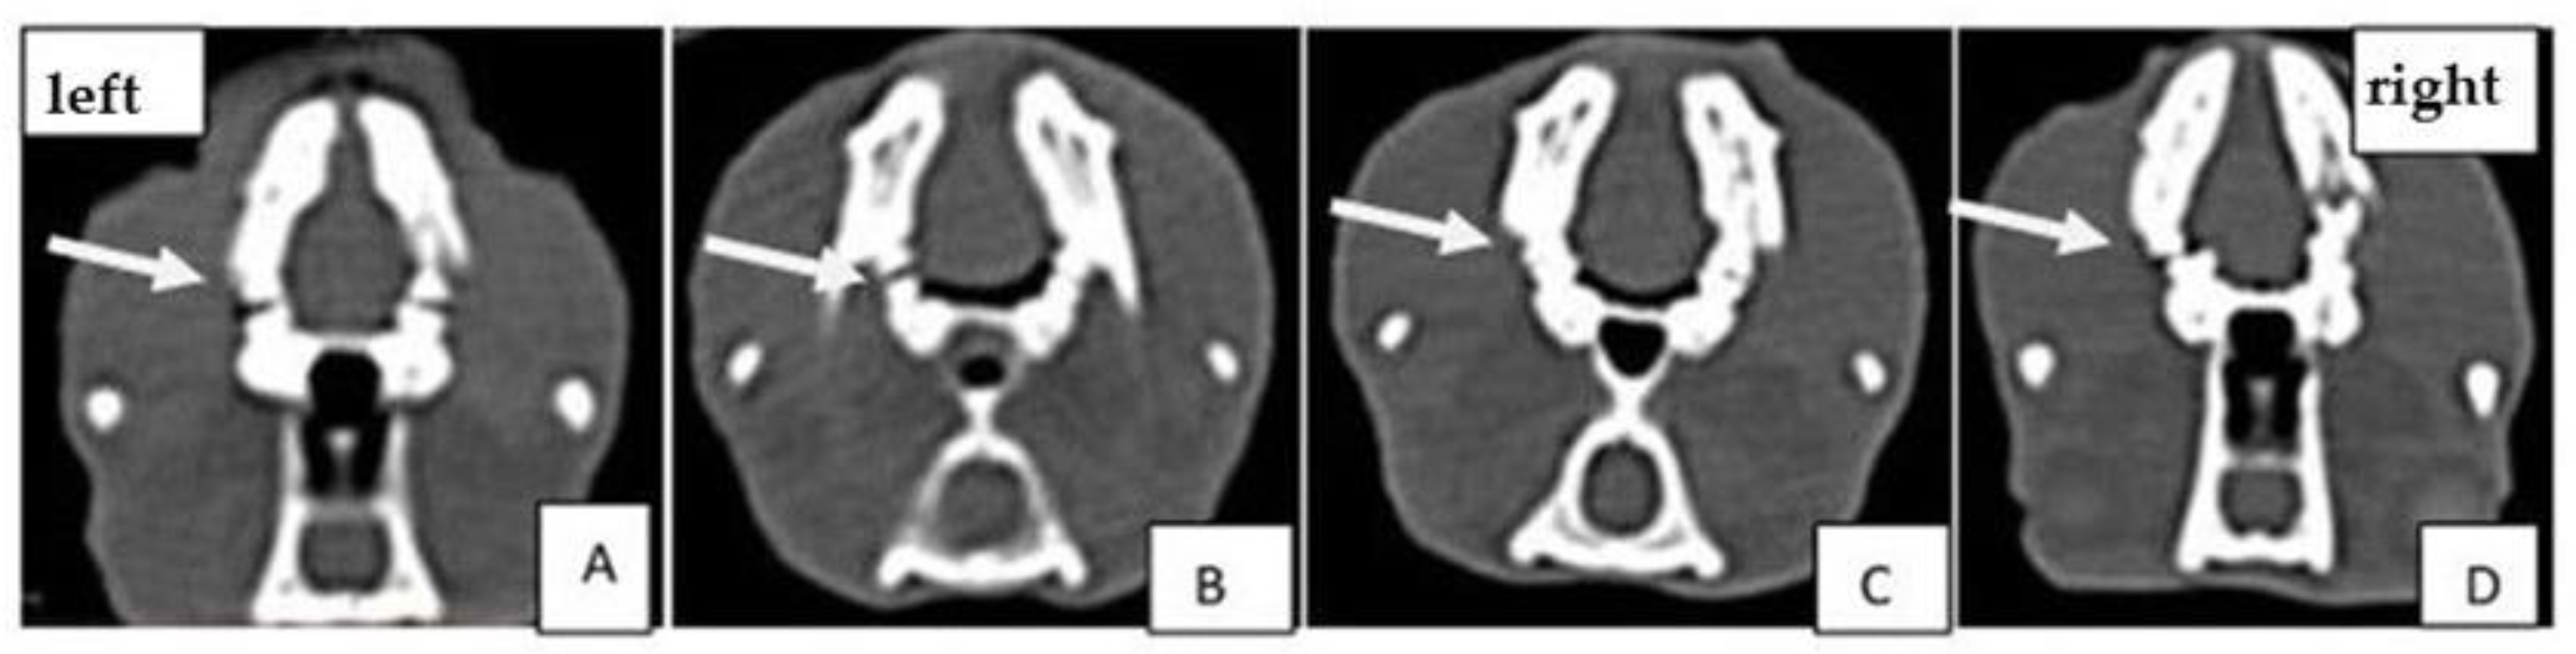

2.3. Computed Tomography (CT) Analysis

4.4. Computed Tomography (CT) Analysis